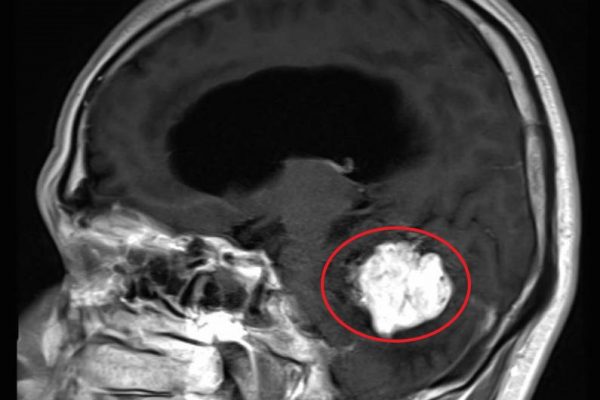

松果体は、脳幹後方に存在する非常に深いところに位置する器官で、ホルモンと呼ばれる人体に必要なタンパク質を分泌する組織です。このページでは松果体にできる腫瘍について治療から合併症についてまで詳しく説明していきます。